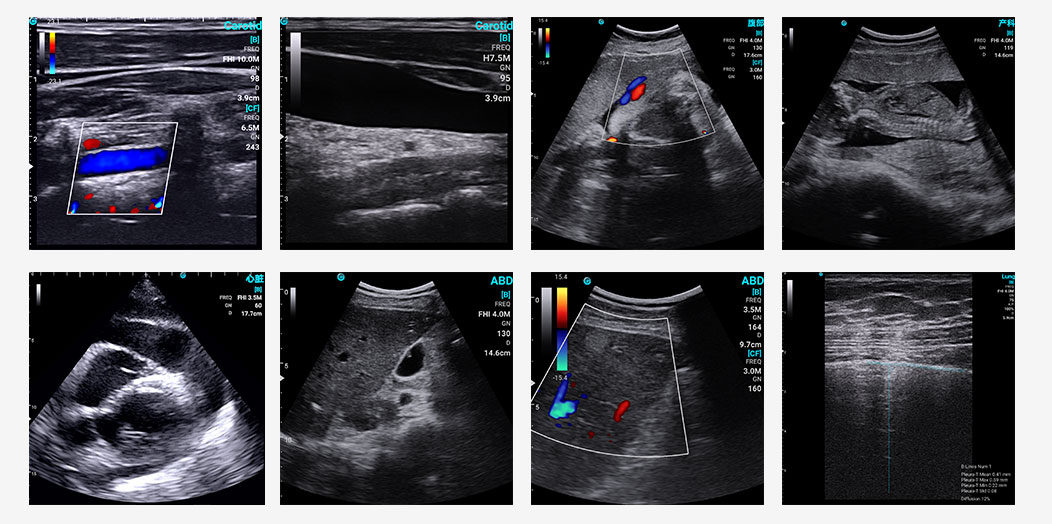

Exemplary sonographic images of SonoEye in B mode, C mode

SonoEye stood out in B-mode image quality, ranking among the top performers. This is a key factor in its success in clinical applications, as high resolution and optimal contrast are vital for accurate diagnoses. As the study mentioned, a convex transducer delivers superior B-mode images for abdominal ultrasound compared to “all-in-one” transducers designed for multiple clinical applications. SonoEye also boasts competitive image quality in Color Doppler Mode, PW Mode and CPA/DPD Mode, ensuring physicians get precise and clear visuals every time.